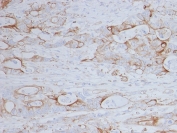

IHC staining of FFPE human colon tissue with recombinant CD151 antibody (clone CD151/9297R). HIER: boil tissue sections in pH 9 10mM Tris with 1mM EDTA for 20 min and allow to cool before testing.